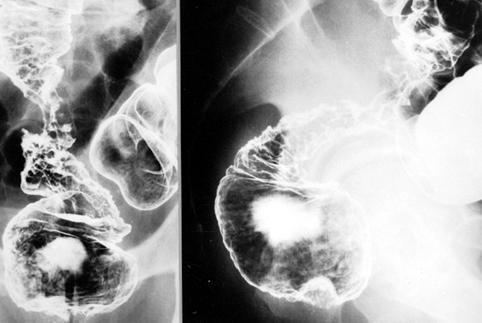

进行性大肠癌4型(弥漫浸润型)

有巨大的皱襞和狭窄范围内的粘膜缺损,因此鉴别为炎症性狭窄性病变,是一例乙状结肠弥漫浸润型(4型)进行性大肠癌

恶性上皮性肿瘤/腺癌

大肠/直肠

X线

4型(弥漫浸润型)/

40以上

s(a)